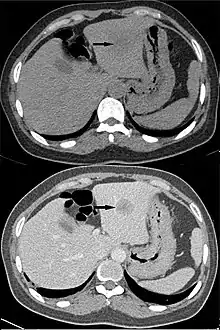

"Washout" is where tissue loads radiocontrast during arterial phase, but then returns to a rather hypodense state in venous or later phases. This is a property of for example hepatocellular carcinoma as compared to the rest of the liver parenchyma.[3]